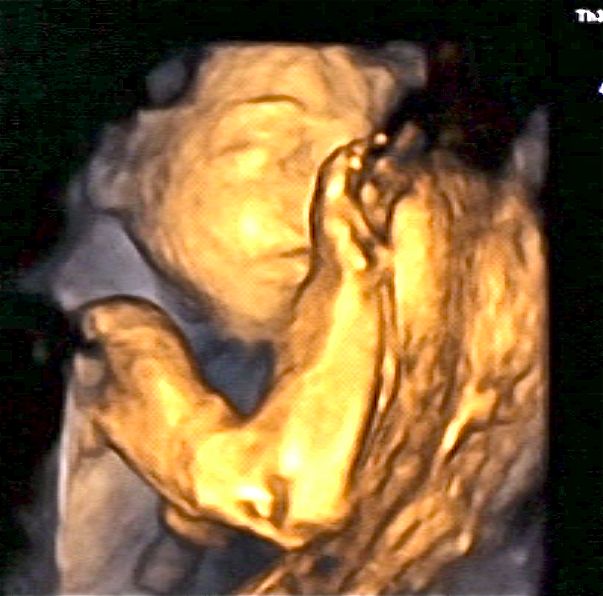

Did the 3d ultrasound today and it was very cool to see her little face for the first time, jeff says she has my nose?? =) everything looks great, she weights about 1'lb and 9oz and measures about 11'inch so far. The ultrasound tech had Jeff push down on a part of my belly and as he was doing that, you could see it on the monitor and she punched back, so cool how you can interact with them already!! Ha ha it felt like we were on skpe with her without the sound, i have the whole DVD but have to figure out, how to load it on you tube then here, but for now here are some pictures from today! ![]() |

| fist in front of face |